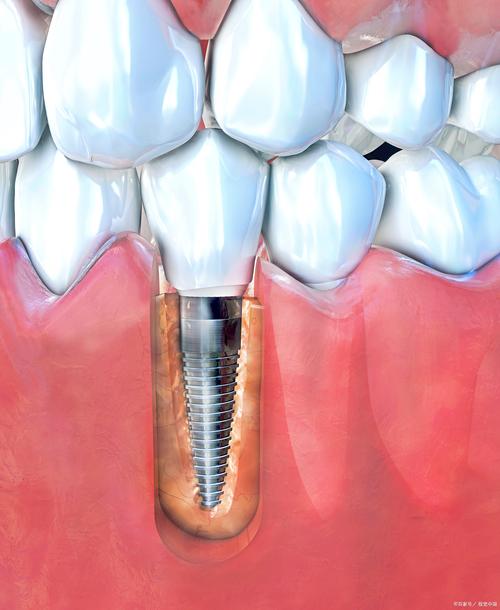

数字化种植技术应用:

- 较大的连锁机构通常具备引进先进数字化设备的能力,如:

- 口腔CBCT(锥形束CT): 进行三维影像检查,精准评估牙槽骨的高度、宽度、密度,避开重要神经血管。

- 口内扫描仪: 取代传统取模,获取精准的数字化模型,提高种植导板和修复体的精确度。

- 数字化种植导板: 利用CBCT数据和口扫模型,在电脑上预先规划种植位置、角度、深度,并制作3D打印导板,实现精准、微创、快速的种植手术。

- 优势: 提高手术安全性、精准度、可预测性,减少创伤和手术时间,提升患者舒适度。